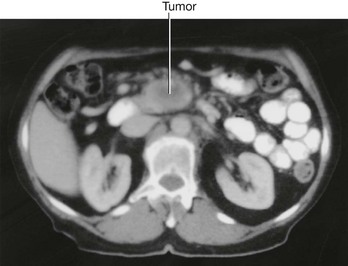

Urinary tract cancer

Most tumors that arise in the kidney are renal cell carcinomas. These tumors develop from the proximal tubular epithelium. Approximately 5% of tumors within the kidney are transitional cell tumors, which arise from the urothelium of the renal pelvis. Most patients typically have blood in the urine (hematuria), pain in the infrascapular region (loin), and a mass.

Renal cell tumors are unusual because not only do they grow outward from the kidney, invading the fat and fascia, but they also spread into the renal vein. This venous extension is rare for any other type of tumor, so, when seen, renal cell carcinoma should be suspected. In addition, the tumor may spread along the renal vein and into the inferior vena cava, and in rare cases can grow into the right atrium across the tricuspid valve and into the pulmonary artery (Figs. 4.142 and 4.143).

Fig. 4.142 Tumor in the right kidney growing toward, and possibly invading, the duodenum. Computed tomogram in the axial plane.

Treatment for most renal cancers is surgical removal, even when metastatic spread is present, because some patients show regression of metastases.

Transitional cell carcinoma arises from the urothelium. The urothelium is present from the calices to the urethra and behaves as a “single unit.” Therefore, when patients develop transitional carcinomas within the bladder, similar tumors may also be present within upper parts of the urinary tract. In patients with bladder cancer, the whole of the urinary tract must always be investigated to exclude the possibility of other tumors (Fig. 4.144).

Fig. 4.144 Transitional cell carcinoma in the pelvis of the right kidney. Coronal computed tomogram reconstruction.